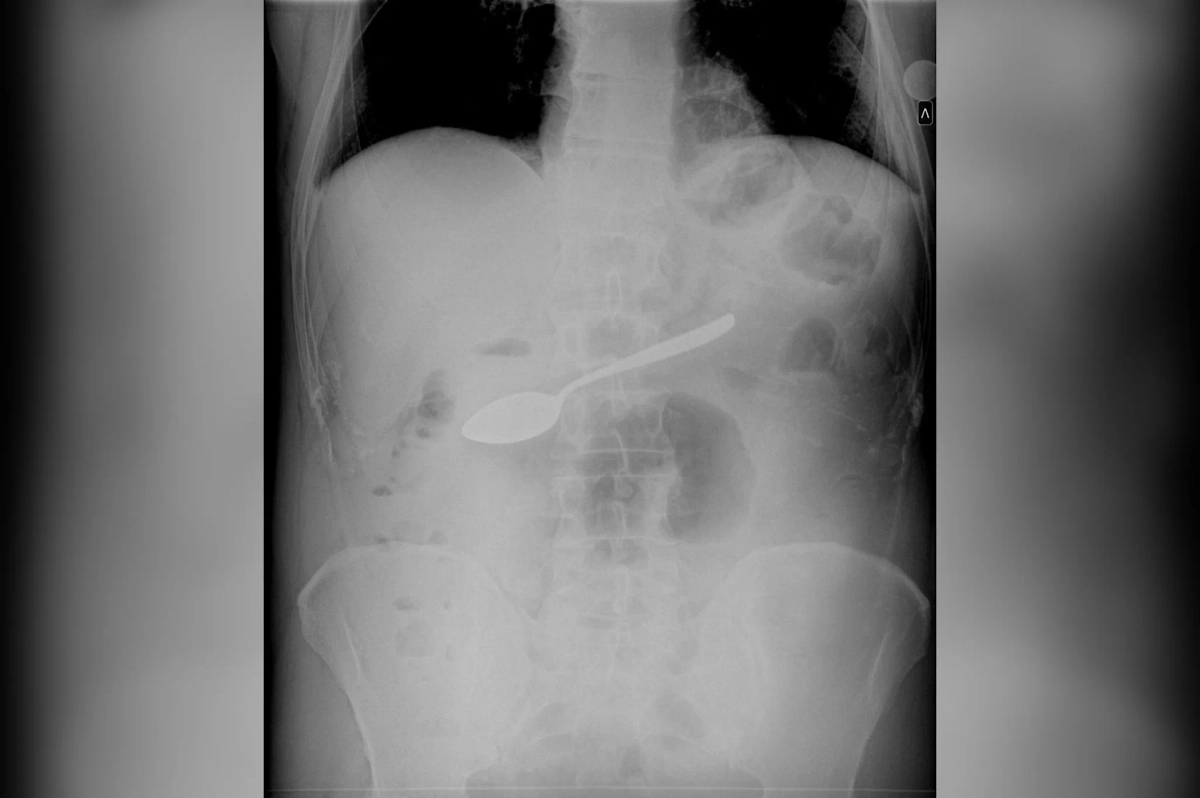

Подмосковные врачи спасли мужчину, который проглотил десертную ложку

Рентген. Обложка © mz.mosreg.ru

В Мытищинской больнице врачи столкнулись с необычным случаем: у пациента в желудке обнаружили десертную ложку. Как именно этот предмет оказался в желудке мужчины, остаётся неизвестным, сообщили в пресс-службе регионального минздрава.

Пациент поступил в больницу с жалобами, и после проведения необходимых обследований врачи установили наличие инородного предмета. Сразу же было принято решение извлечь его, чтобы избежать осложнений. Медики выбрали менее инвазивный метод — извлечение ложки через пищевод с использованием специального зажима. Это позволило избежать проведения открытой операции и минимизировать риски для здоровья пациента.

Операция прошла успешно: ложка была извлечена без повреждений внутренних органов. Несмотря на сложность процедуры, врачи справились с задачей на высоком уровне. На данный момент информации о состоянии пациента после процедуры нет, но специалисты уверены, что своевременное вмешательство предотвратило возможные осложнения.